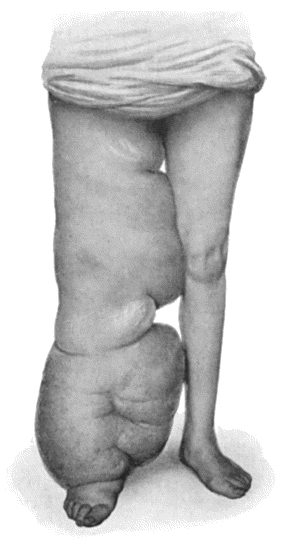

89.Elephantiasis Neuromatosa in a woman æt. 28 359

97.Elephantiasis in a woman æt. 45 387